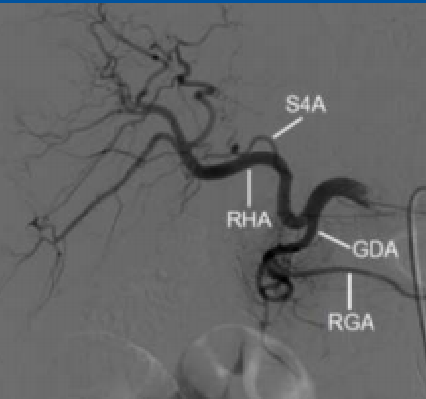

| 挽救性CRC,多灶性,肝右叶病灶一次性治疗 scout dose (低剂量或侦查剂量)右肝动脉【Nima Kokabi 2022 最新的进展】

注意肝左动脉(特别是,异位肝左动脉(replaced left hepatic artery))

有问题的血管